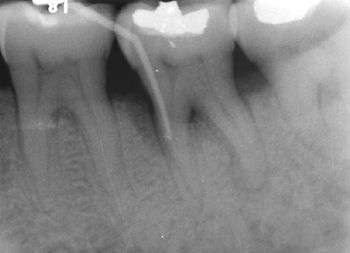

Furcation defect

In dentistry, a furcation defect is bone loss, usually a result of periodontal disease, affecting the base of the root trunk of a tooth where two or more roots meet (bifurcation or trifurcation). The extent and configuration of the defect are factors in both diagnosis and treatment planning.[1]

Because of its importance in the assessment of periodontal disease, a number of methods of classification have evolved to measure and record the severity of furcation involvement; most of the indices are based on horizontal measurements of attachment loss in the furcation.

- Grade I - Incipient furcation involvement, with an associated periodontal pocket remaining coronal to the alveolar bone. The pocket primarily affects the soft tissue. Early bone loss may have occurred but is rarely evident radiographically.

- Grade II - There is a definite horizontal component to the bone loss between roots resulting in a probeable area, but sufficient bone still remains attached to the tooth (at the dome of the furcation) so that multiple areas of furcal bone loss, if present, do not communicate.

- Grade III - Bone is no longer attached to the furcation of the tooth, essentially resulting in a through-and-through tunnel. Because of an angle in this tunnel, however, the furcation may not be able to be probed in its entirety; if cumulative measurements from different sides equal or exceed the width of the tooth, however, a grade III defect may be assumed. In early grade III lesions, soft tissue may still occlude the furcation involvement, thus, making it difficult to detect.

- Grade IV - Essentially a super grade III lesion, grade IV describes a through-and-through lesion that has sustained enough bone loss to make it completely probeable.